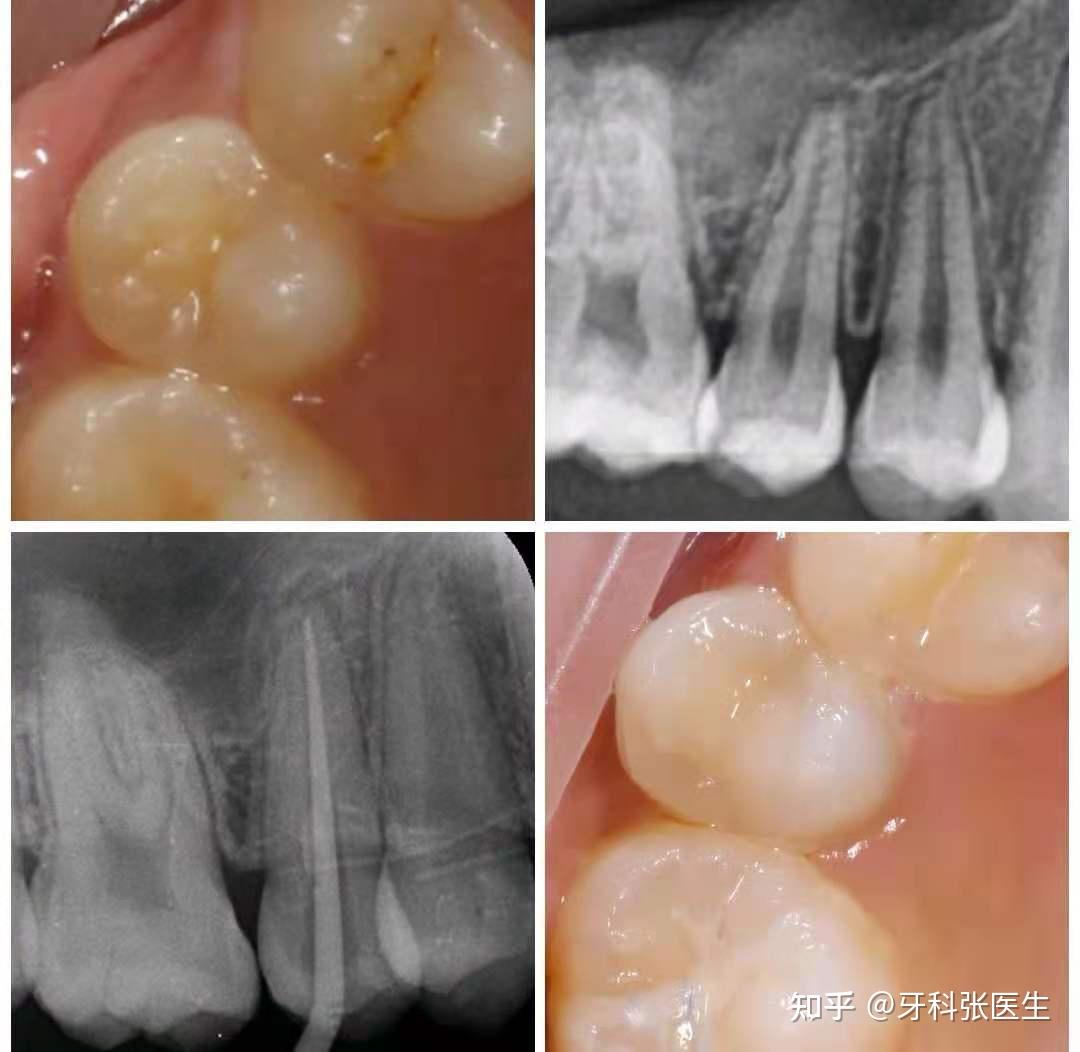

窝沟封闭前后对比图--为宝宝的牙齿穿上铠甲|根栏目|陕西嘉友科贸有限